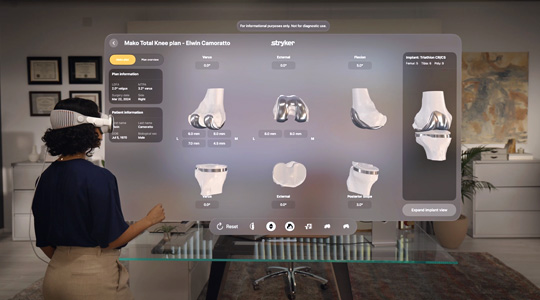

Work with everyday business apps in an unlimited, interactive space. Streamline collaboration with Microsoft 365 Copilot, Zoom, and Webex. Accelerate data analysis and visualization at scale with platforms like SAP, Salesforce, and NVIDIA Omniverse. And bring projects and training programs to life with incredible visionOS apps that are ready for enterprise.